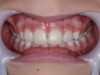

Lorenzo 10 ans : 6 mois d'éducateur fonctionnel